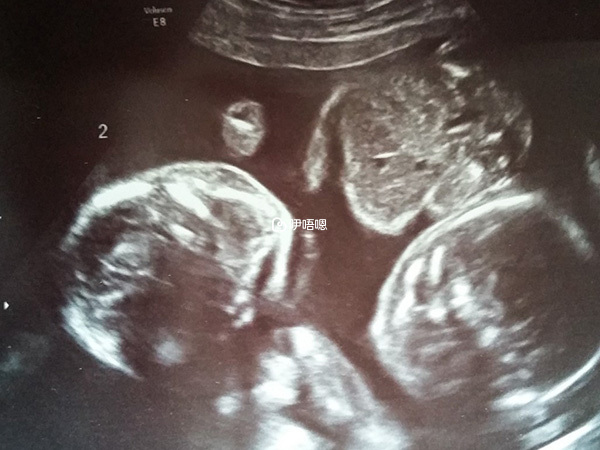

曾經有過四次人流史,一次4個半月胎膜早破自然流產;婚後半年不孕,造影查出單角子宮以及輸卵管積水。單角子宮,最大B超值11點多,最小的值才9點多;曾經吃積水藥方三個月,結合跳繩、外敷、灌腸。因為太辛苦,而且不知道是否有用,對著急生BB的我們來說等不起這個未知數,於是決定試管。我促排一次,取11個卵,配成8個,移植三次(因為B超照不到積水,醫生說積水不用去管,所以沒有抽水),第三管成功。12天有褐色分泌物,分泌物持續一個月,整個懷孕過程無其他意外。

兒子出生5斤,女兒4.6斤,出血400CC,評分10,未住保溫箱,一切很順利。手術中醫生說我有殘角,我問要割掉麼,醫生說如果不打算生就不要割了,於是就沒管了。